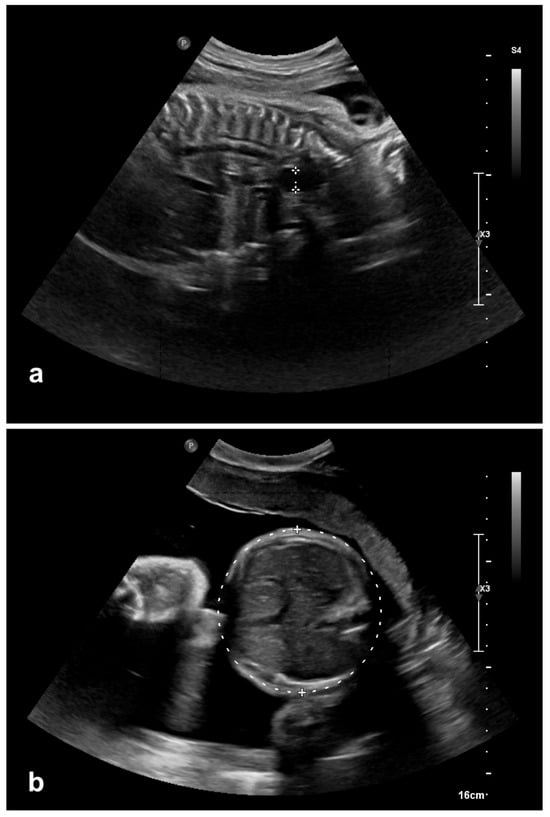

On the first day of life an upper gastrointestinal (GI) series was performed, since esophageal atresia had been suspected. A water-soluble contrast agent was applied via a nasogastric tube. The images showed a contrast-stained esophageal pouch ending in the upper mediastinum (Figure 2). In addition, a round gas-filled structure was located in the middle lower mediastinum measuring 3 × 2.4 cm with a broad base at the level of the diaphragm. These findings indicated esophageal atresia with an intrathoracic stomach. The neonate remained clinically stable.

Figure 2. Contrast-stained esophageal pouch with the nasogastric tube, as well as the gas filled intrathoracic stomach.